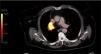

Radiología (English Edition) European Diploma in Radiology (EDiR) clinical cases

Case for diagnosis

European Diploma in Radiology (EDiR) clinical cases